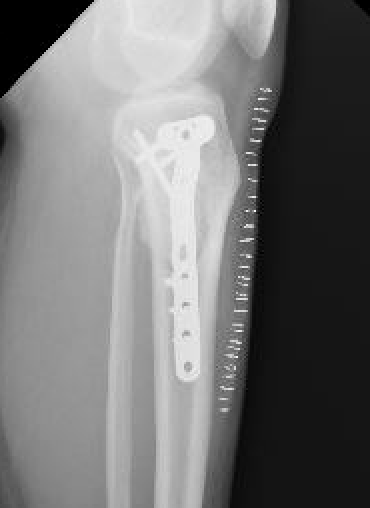

Management

Intra-lesional curettage & bone grafting / cement

Recurrence common (25%)

Treat recurrence with wide resection